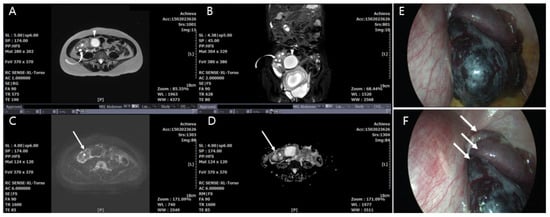

4.5. MRI Findings by a Multiparameter Imaging